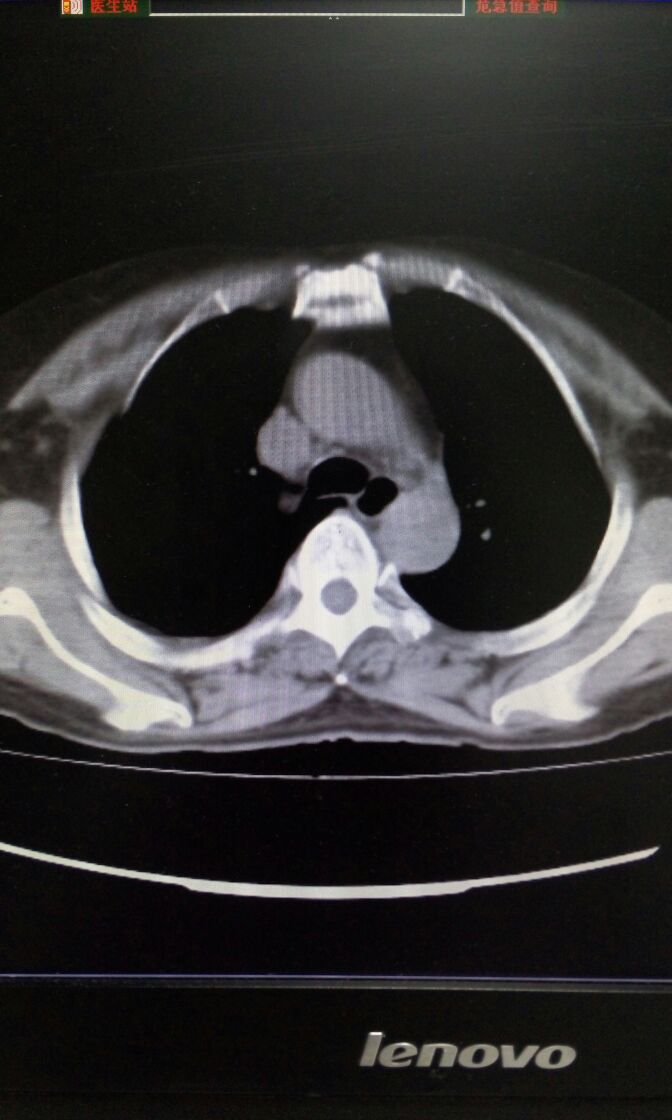

女,65岁,头痛、发热畏寒伴咳嗽咳痰1周。咽拭子流感A抗原阳性。肺部CT如图。诊断和治疗?

女,65岁,头痛、发热胃寒伴咳嗽咳痰1周。咽拭子流感A抗原阳性。肺部CT如图。诊断和治疗?补充纵膈窗